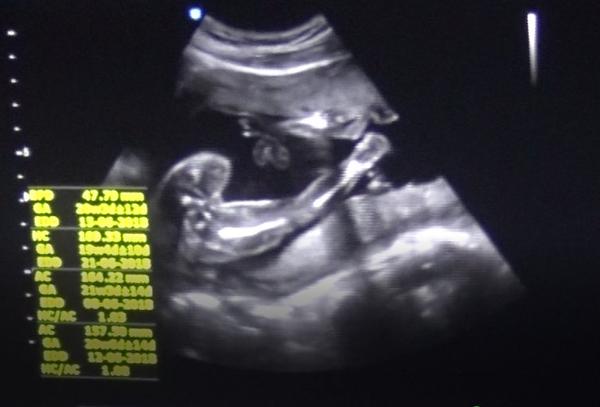

U nás taky hodně lidí nelékařů tipovalo kluka podle této mojí fotky (moji doktoři mi to řekli až tak v 34tt, bylo to s nimi komplikované, chtěli megasuperhyper VIP poplatky)... no a máme princeznu 🙂 Takže zatím nezoufej, třeba to holka bude 🙂 Z fotky se to obecně hůř pozná než třeba z videa, jsou tam různé stíny, průřezy apod.

@zouzalka1982 tady posílám potvrzenou holčičku

@zouzalka1982 určitě dej vědět. Všichni říkali, že u holčiček je vidět kávový zrno. No, u té mojí mi to zrno ani při troše fantazie nepřipomíná. Ale holčička to nejspíš opravdu bude. Už mi ji od cca 16tt řekli 3 doktoři. Nikde nic netrci, tak to snad bude. Jistota samozřejmě bude až po porodu.